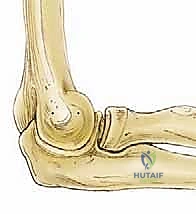

يتكون المرفق فعلياً من ثلاثة مفاصل فرعية تعمل بتناغم تام داخل كبسولة مفصلية واحدة:

هو المفصل الأساسي المسؤول عن حركتي الثني (Flexion) والمد (Extension). يتكون من تمفصل البكرة العضدية مع الثلمة البكرية لعظمة الزند. يمر محور دورانه الثابت عبر اللقيمة الوحشية وأمام وأسفل اللقيمة الإنسية مباشرة. هذا التصميم الهندسي يوفر استقراراً جوهرياً عالي الكفاءة، مما يمنع الحركات الجانبية المفرطة. - المفصل الكعبري الزندي القريب (Proximal Radioulnar Joint):

هذا المفصل هو المسؤول عن حركات دوران الساعد؛ الكب (Pronation - توجيه راحة اليد للأسفل) والاستلقاء (Supination - توجيه راحة اليد للأعلى). - المفصل الكعبري الرأسي الصغير (Radiocapitellar Joint):

هنا يكمن بيت القصيد في موضوعنا. في هذا المفصل، يتصل الرأس الصغير (Capitellum) المستدير والمحدب للعظم العضدي البعيد مع الرأس الكعبري (Radial Head) المقعر. هذا المفصل يتحمل العبء الأكبر من قوى الضغط المحوري. عادةً ما يظهر المفصل الزندي العضدي بزاوية وحشية (Valgus Angle) تتراوح بين 11 و16 درجة. هذه الزاوية الطبيعية تؤدي إلى تركز قوى الضغط تحديداً في الجانب الوحشي (الخارجي) للمرفق أثناء الأنشطة الرياضية أو حمل الأشياء الثقيلة. هذا الضغط المتكرر والعنيف هو العامل الميكانيكي الرئيسي في نشأة التهاب العظم والغضروف السالخ (OCD).